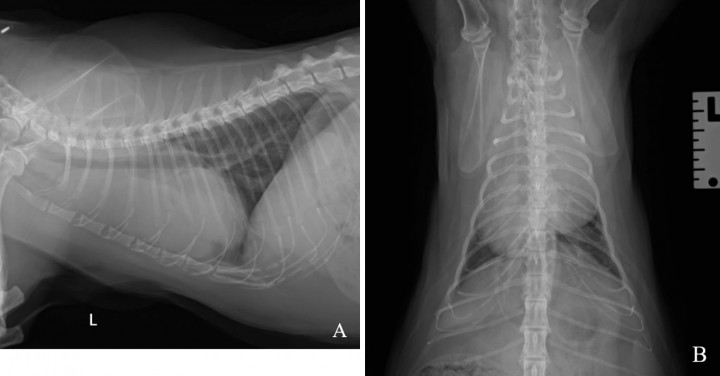

Acudió a consulta una gata de 10 años castrada de raza Himalaya remitida de su clínica veterinaria habitual por un episodio de síncope. La exploración física general realizada en consulta fue compatible con la normalidad. Se realizó analítica sanguínea completa donde la bioquímica era normal; sin embargo, en el hemograma se observó leucocitosis linfocítica (leucocitos 23,24 K/µl, valor de referencia: 2,87-17,02 K/µl; linfocitos 14,83 K/µl, valor de referencia: 0,92-6,88 K/µl). Se realizaron radiografías de tórax en proyecciones laterolateral izquierda y ventrodorsal (Fig. 1).

<p>Radiografías de tórax. (<strong>A</strong>) Proyección laterolateral izquierda. (<strong>B</strong>) Proyección ventrodorsal.</p>

Radiografías de tórax. (A) Proyección laterolateral izquierda. (B) Proyección ventrodorsal.